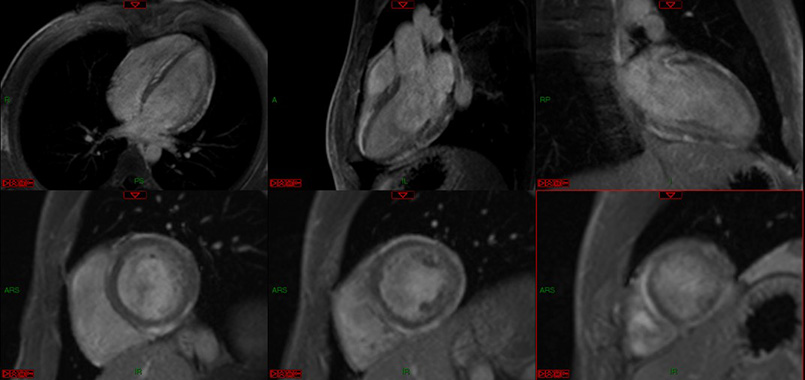

CAZ: IRM de stres cu adenozina la un pacient in varsta de 59 de ani, cu multipli factori de risc cardiovascular, cu episoade de angina la efort, la care examinarea ecocardiografica a decelat hipokinezie de perete inferior. Pe imaginile de perfuzie la stres, se deceleaza anomalie de perfuzie la nivelul segmentelor inferobazal si inferoseptal bazal (ceea ce traduce imagistic prezenta ischemiei indusa farmacologic in teritoriul arterei coronare drepte = test „de stres” pozitiv).